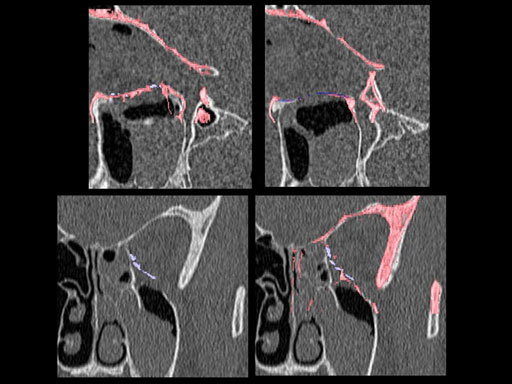

Furthermore, as orbital floor fractures are quite frequently associated with medial wall fractures; anatomic restoration especially in the transition zone between both wall is a demanding procedure. As described by B. Hammer, the orbital floor has an initial shallow convex section behind the rim, then inclines upward behind the globe, and inclines upward to meet the medial wall, creating a distinct bulge behind the globe. These convex curves of the medial wall and floor create a postbulbar constriction of the orbital cavity, which must be reconstructed when the orbit is rebuilt following fractures. Treatment is directed at precise anatomical reconstruction of orbital shape and volume in order to restore the correct position of the eye. To provide surgeons with an adequate implant that addresses the requirements of two wall acute orbital fractures or for secondary reconstruction of enophthalmos and dystopia, a new series of preformed orbital plates was developed for the new orbital matrix system.

Unlike the existing two-dimensional mesh implants, the geometry of the new preformed plates will be adequate to match the individual anatomic situation of the patient in almost any case. However, the mesh parts can be individually adjusted if necessary. In these cases the solid part in the central posterior area needs to remain untouched. Areas of the orbit that do not require a bridging can be spared out by trimming the implant along the designated cutting lines in the height of the medial wall and/or length of the orbital floor area. The lateral anterior part of the plate is intentionally pre-bent higher than the orbital rim anatomy to allow free plate movement during plate positioning.

The Preformed Orbital Plates are indicated for trauma repair and reconstruction of fractures of the orbital floor, medial orbital wall or combined fractures of floor and medial wall. It should be noted that in three-wall fractures where the lateral wall is also involved, a second orbital implant, ( i. e. the mesh plate) must be used in addition to the pre-formed orbital plate.

Implant placement according to the orbital landmarks

1 Orbital rim, 2 Inferior orbital fissure, 3 Posterior orbital ledge, 4 Transition between the medial wall and orbital floor, 5 Optic canal, 6 Lacrimal fossa

30 year old male patient with fracture of left orbital floor and medial wall.

Provided by Dr Dr Marc C Metzger, Freiburg, Germany.